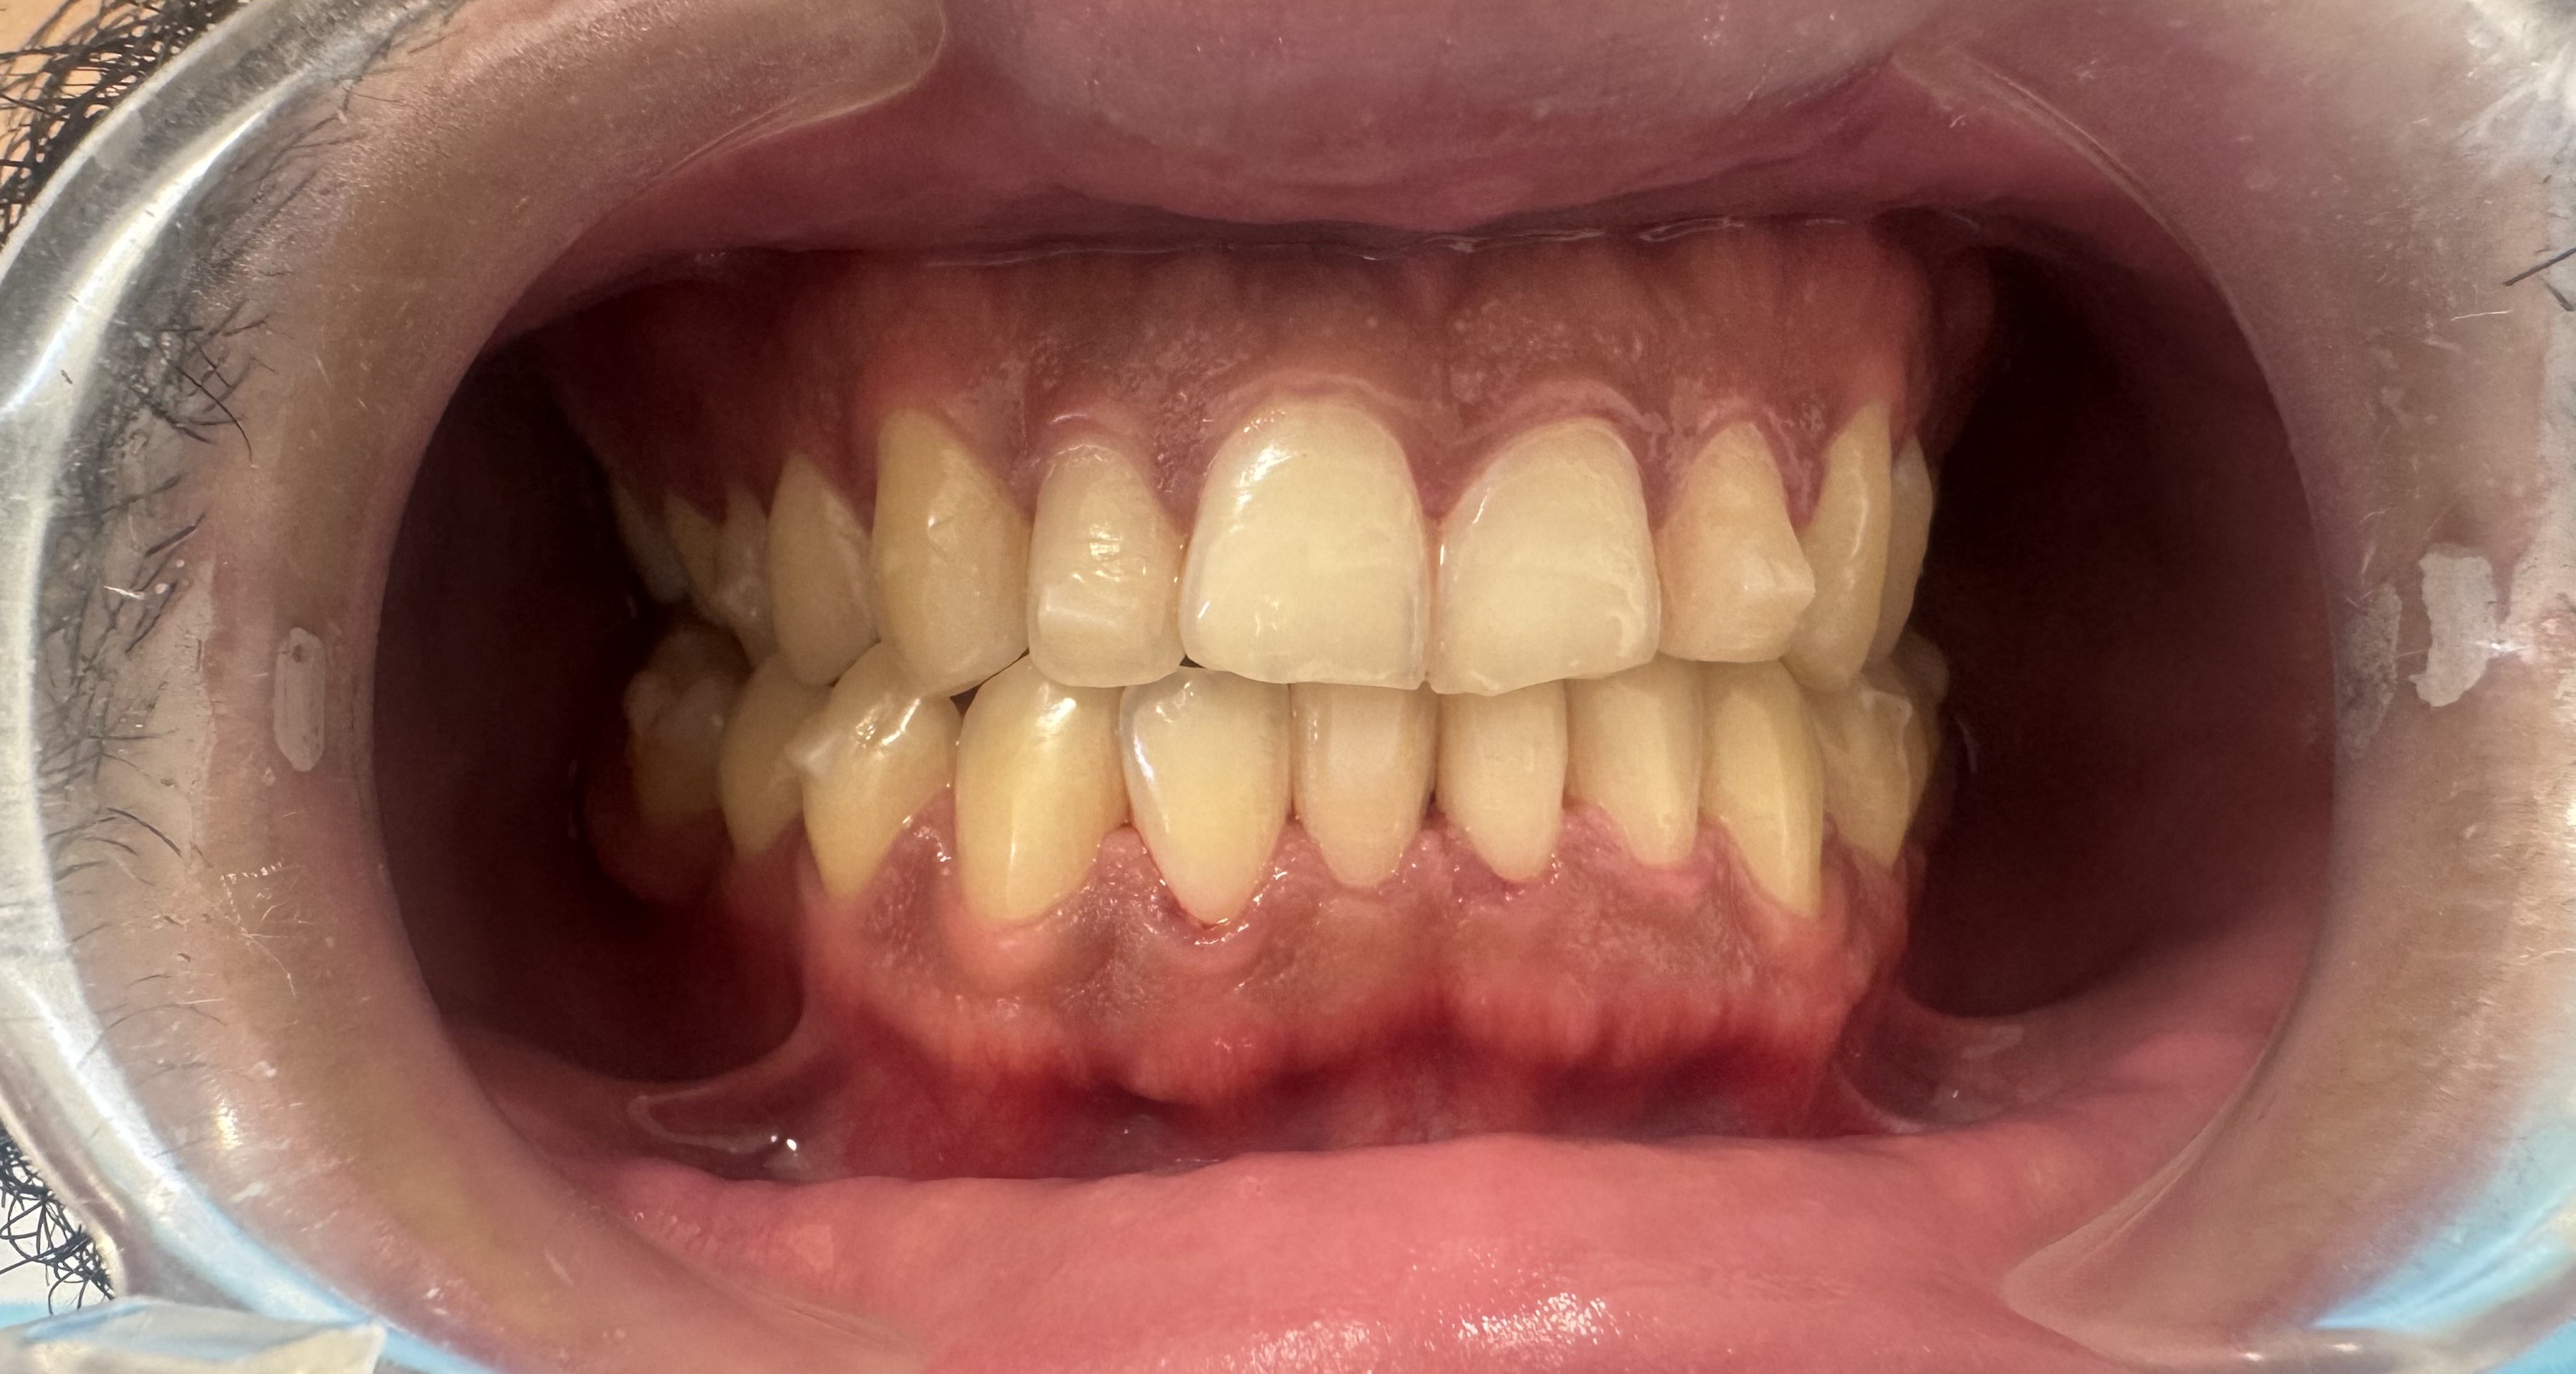

After